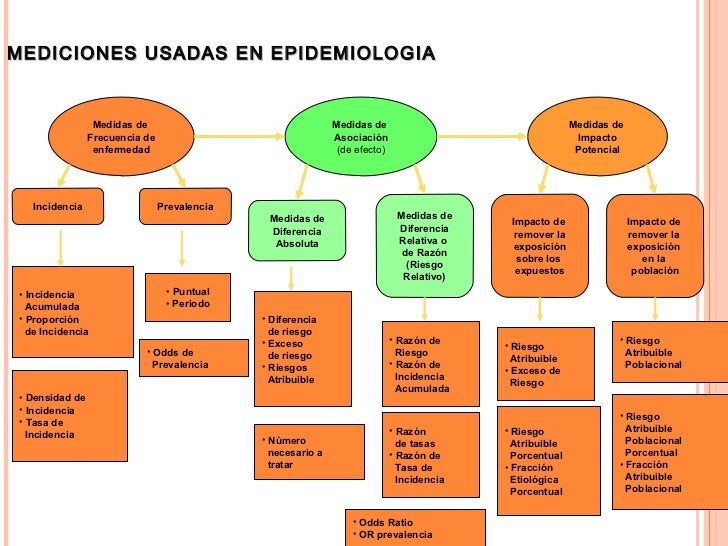

Criterios de las medidas epidemiológicas

Según la Organización Panamericana de la salud (2011). Se dividen en:

Medidas de frecuencia: Se emplean para medir la frecuencia de enfermedades de una población y es una tarea fundamental. Para realizar esta medición se emplean tres conceptos muy importantes: probabilidad, riesgo y tasa.

Probabilidad: Es una medida de ocurrencia de un hecho incierto, es decir el número de veces que se espera ocurra un evento a futuro.

Riesgo de la salud: Es una medida que refleja la probabilidad que se produzca un daño a la salud en un periodo de tiempo determinado.

Tasa: Es una medida de la rapidez de cambio de un estado a otro, (como por ejemplo de sano a enfermo) y por tanto también expresa un riesgo.

Las medidas que se emplean para medir la frecuencia son prevalencia e incidencia:

Prevalencia: Es la medida del número total de casos existentes, llamados casos prevalentes, de una enfermedad en punto o un periodo de tiempo y en una población determinada, sin distinguir si son o no casos nuevos. Es necesario destacar que la prevalencia es un indicador de la magnitud de la presencia de una enfermedad u otro evento en la población.

Incidencia: Es la medida del número de casos nuevos, llamados casos incidentes, de una enfermedad originados en una población en riesgo de padecerla, durante un periodo de tiempo determinado. La incidencia es un indicador de la velocidad de ocurrencia de una enfermedad u otro evento en la población y por ende, es un estimador de riesgo absoluto de padecerla.

Medidas de asociación: Se aplican con la intención de establecer una relación de causa y efecto entre una exposición y una enfermedad o evento en salud, sin embrago debe tomarse en cuenta que una asociación puede ser fortuita o puede ser producida por varios eventos y por lo tanto, la presencia de una asociación estadística no necesariamente implica una relación casual.

Para explorar una posible asociación entre exposición y enfermedad se requiere emplear tres elementos: dos grupos comparables de la población, una medida de variable exposición para cada grupo y una medida de la variable enfermedad en cada grupo. En general las variables epidemiológicas de exposición y enfermedad son continuas o discretas y sus medidas se resumirán en promedios o en proporciones. Cabe señalar que las medidas de asociación se basan en las llamadas pruebas de significancia; cuyo propósito es determinar si la presencia de un factor de riesgo evaluado esta efectivamente relacionado con la frecuencia de la enfermedad. En este tipo de medidas se emplea la prueba de chi cuadrado, pues mediante esta es posible comparar dos proporciones

Medidas de impacto

Riesgos atribuibles: Es la magnitud absoluta de la incidencia de enfermedad que se atribuye a la exposición, pero no solo en los expuestos, sino en el conjunto d la población.

Fracciones atribuibles: Es una medida que cuantifica el exceso de riesgo de enfermar, que se atribuye a la exposición, no solamente en los expuestos, sino en el conjunto de la población.

Estandarización de tasas: Las tasas se presentan para la población completa o para grandes categorías de la misma. A estas tasas se les denominan tasas crudas. Cabe destacar que las tasas también pueden ser presentadas en forma desagregada para varias categorías de población, definidas sobre la base de características relevantes a la comparación, tales como edad, sexo, etnia, ocupación o nivel de exposición a determinado factor de riesgo. A estas tasas se les denomina tasas específicas.

Es necesario mencionar que para poder realizar comparación libre de las distorsiones que pueden provocar las diferencias en la composición de la población, se deben emplear tasas estandarizadas, que son tasas construidas estadísticamente para tomar en cuenta y promover el potencial efecto confusor de la variable edad u otra tercera variable, al comparar las tasas de mortalidad o incidencia de dos poblaciones diferentes. El procedimiento básico para el ajuste de tasas requiere contar con las tasas específicas por categoría de la variable a ajustar en ambas poblaciones a comparar.